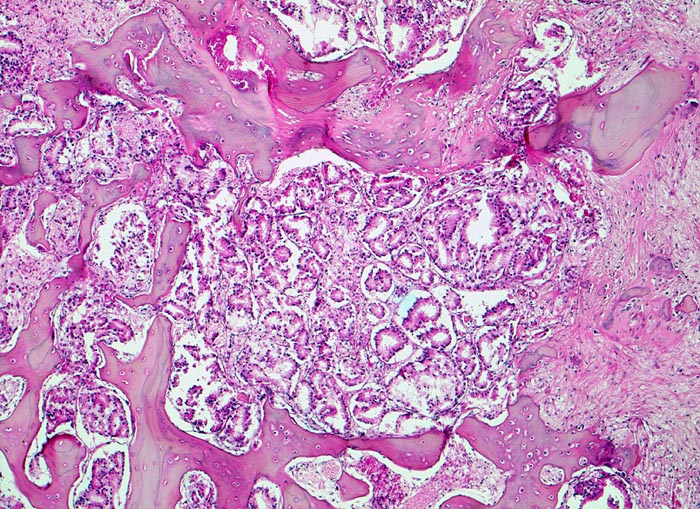

Prostatakarzinom: Knochenmetastase

Im Zentrum die kleinen dicht liegenden Karzinomdrüsen. Der Knochen wird stellenweise abgebaut. Fokal ist eine Faserknochenneubildung erkennbar.

Bei Autopsie finden sich zahlreiche, teils osteoplastische, teils osteolytische Metastasen im Bereich der Wirbelsäule. Die Karzinomdrüsen sind immunhistochemisch positiv für Prostata spezifisches Antigen.

Bekanntes metastasierendes Prostatakarzinom. St.n. bilateraler Orchiektomie. Diffuse Schmerzen im Bereich der Wirbelsäule. Der Patient verstirbt an einem Myokardinfarkt.